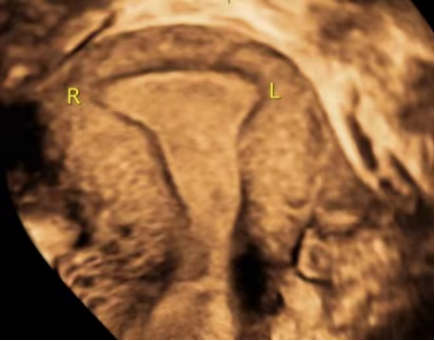

怎么来判断土壤是肥沃还是贫瘠呢?这就需要进行子宫三维容受性超声检查来评估。

2. 子宫内膜类型:在超声下,子宫内膜形态主要分为 A、B、C 三型,其中 A、B 型内膜妊娠率高。

6. 子宫内膜与肌层结合带:观察它的连续性、完整性并测量结合带宫底部和腰部区的厚度。